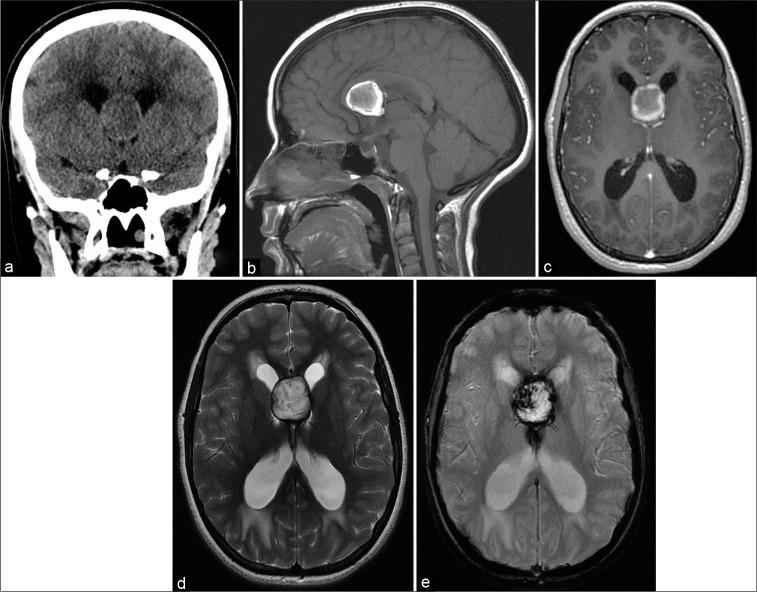

A 16-year-old girl presented with a 1-month history of gradual visual deterioration in the left eye, intermittent headache, and vomiting. Brain imaging showed hematoma located between the leaflets of the septum pellucidum with obstructive hydrocephalus. Transcallosal resection of interventricular mass was done. The patient was discharged with improved neurological symptoms; however, the left eye vision did not recover. Imaging demonstrated a unique anatomical variant in deep vascular structures.

一名16岁女孩,有1个月左眼视力逐渐下降、间歇性头痛及呕吐病史。脑部影像学检查显示血肿位于透明隔小叶之间并伴有梗阻性脑积水。行经胼胝体间脑室内肿物切除术。患者出院时神经症状改善;然而,左眼视力未恢复。影像学显示深部血管结构存在一种独特的解剖变异。